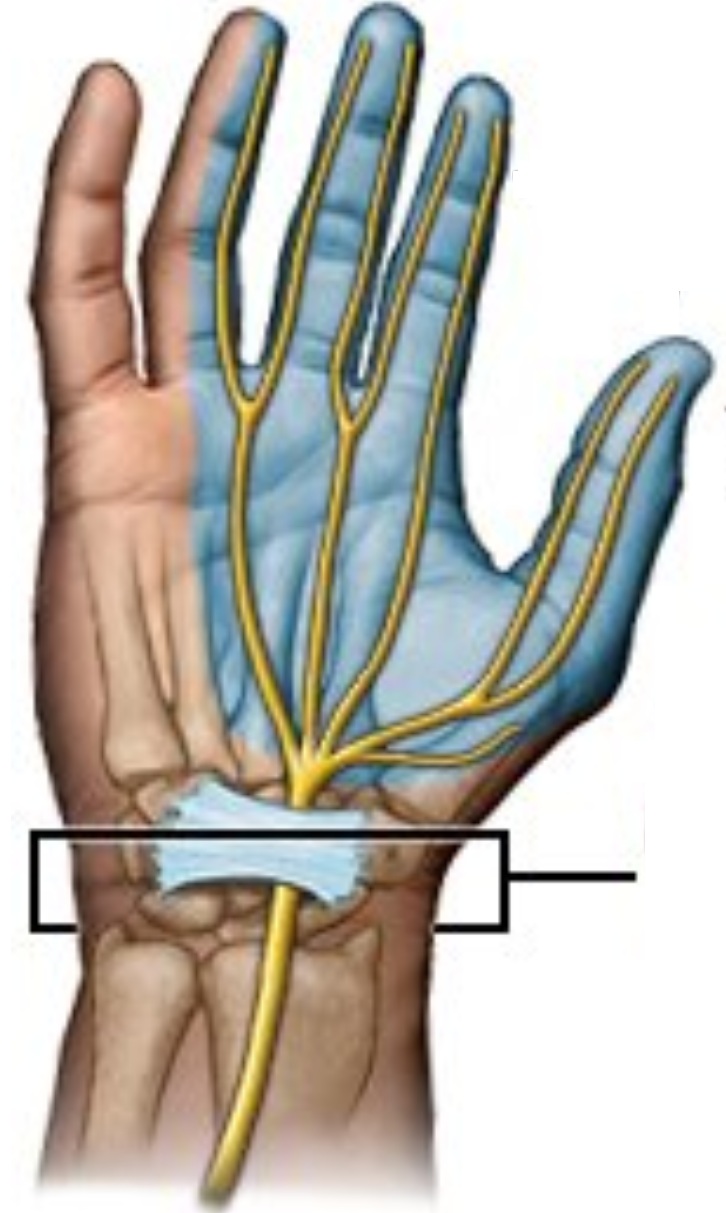

Adormecimiento y dolor en mano, evaluación electrofisiológica y descompresión cuando está indicada.